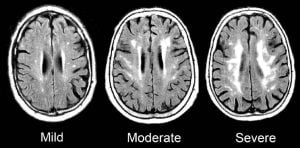

One of the greatest challenges, when it comes to Alzheimer’s disease and other dementias, is coping with sundowning and with difficult behaviors. These are symptoms beyond the chronic memory/thinking problems that…